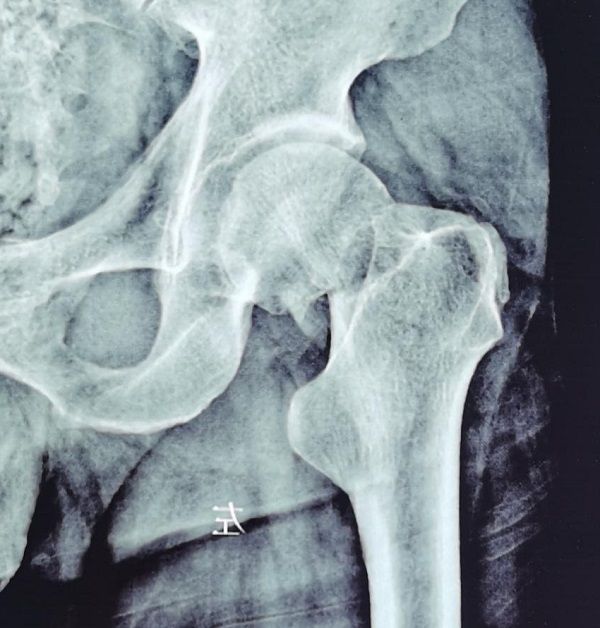

“是截肢,还是保肢?”面对肢体毁损严重的患者,手·显微外科的医生们经常要面对这样的重大选择。 2021年11月的某天,家住礼泉县的寇先生因机器挤压造成右上肢严重损伤,经过消防人员3小时的救援,寇先生被紧急送...